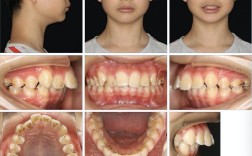

隐形牙套的适用范围与传统正畸有重叠,但也有侧重,并非所有牙齿问题都能仅通过“戴牙套”解决,需结合具体病情判断:

适合“隐形牙套单独解决”的轻度问题

- 牙齿轻度拥挤:门牙、前磨牙等少量牙齿拥挤(拥挤度<4mm),通过隐形牙套的“扩弓”或“邻面去釉”(适当磨除少量牙釉质,为牙齿移动空间)即可改善排列。

- 牙缝过大:先天牙缝宽或牙周治疗后牙缝暴露,通过隐形牙套的“关闭牙缝”功能,将牙齿向中间聚拢。

- 个别牙齿扭转/错位:1-2颗牙齿(如尖牙、前磨牙)轻度扭转、唇倾或舌倾,可通过精准施力调整位置。

- 简单深覆合/深覆盖:上下牙垂直向或水平向覆盖轻微(深覆合<1/3牙冠高度,深覆盖<4mm),通过压低上前牙或推下前牙改善咬合关系。